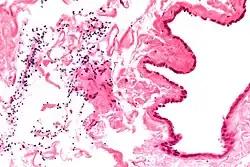

| Ultrasound of a testicle (grey) and a spermatocele (black). | |